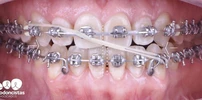

Diş Çapraşıklığı

Implant tedavisi